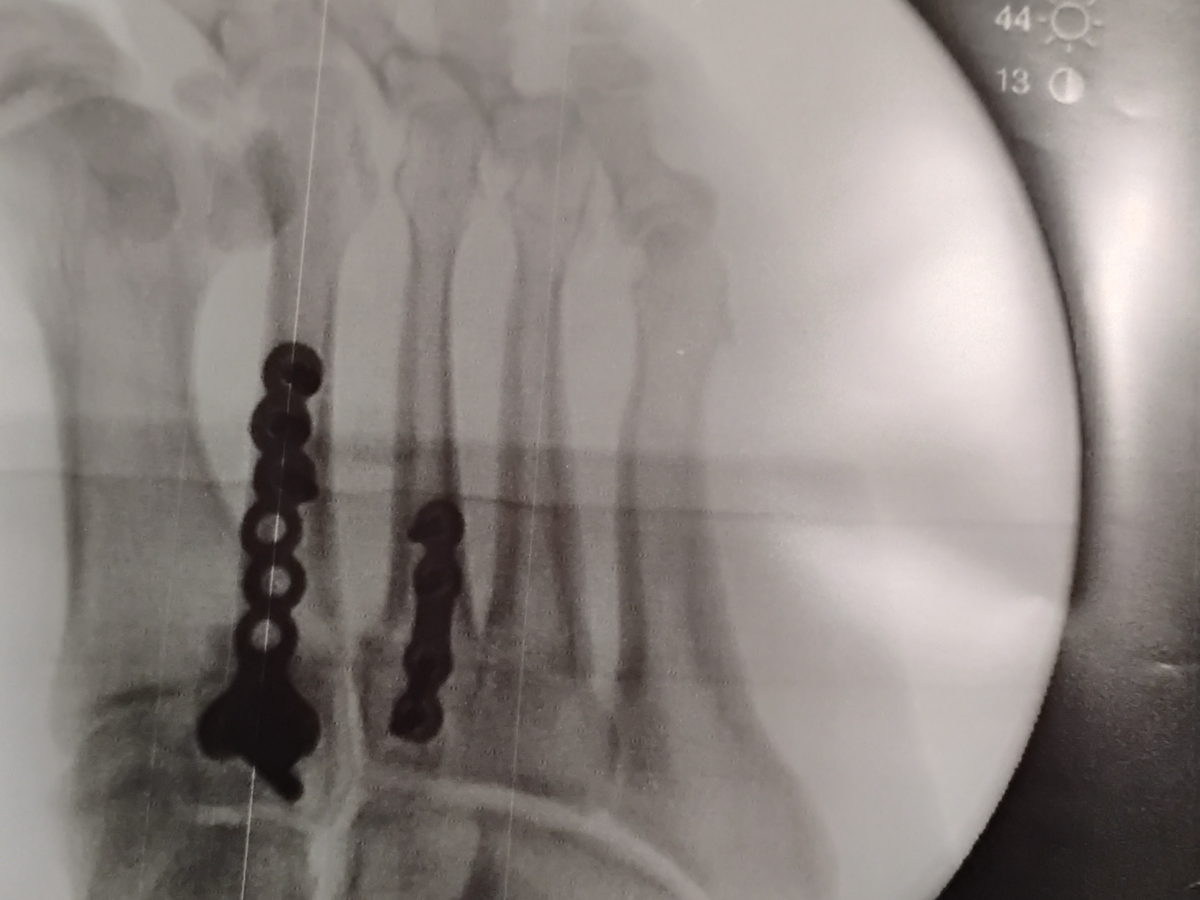

On January 29th my husband Oscar Keith Urquhart had a scissor lift rolled on to the top of his foot and stopped and it broke 3 bones in his foot which he had surgery for on February 27th at this time we do not know when he will be able to return to work